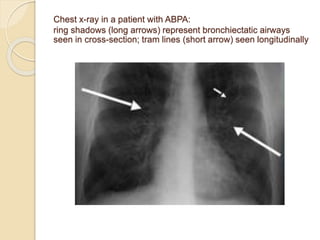

Chest x-ray in a patient with ABPA:

ring shadows (long arrows) represent bronchiectatic airways

seen in cross-section; tram lines (short arrow) seen longitudinally

 Chest radiographic findings

 Permanent changes

◦ Parallel-line shadows representing bronchial widening

◦ Ring-shadows 1–2 cm in diameter representing dilated

bronchi en face